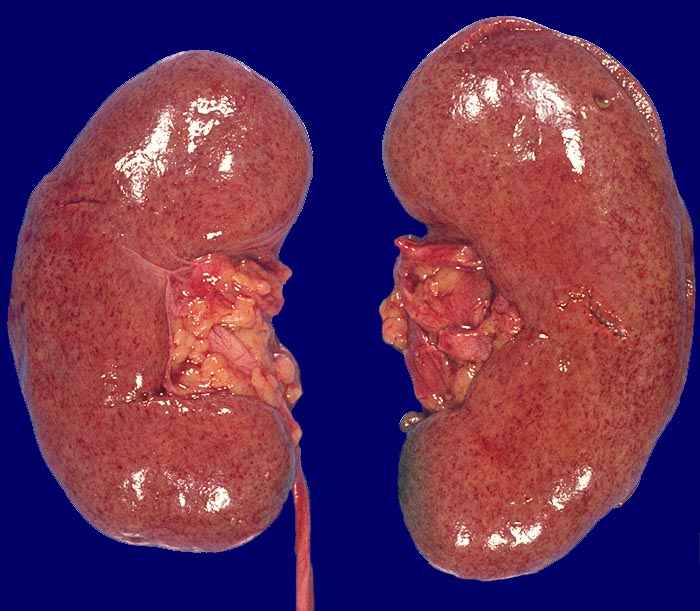

Extrakapillär betonte Glomerulonephritis

Die Nieren sind leicht vergrössert. Die Oberfläche ist glatt und zart. Man erkennt, dass die Oberfläche übersäht ist von kleinsten Petechien.

Definiert als Glomerulonephritis mit Halbmonden in mehr als 50 bzw. 75% der Glomeruli. Die Zusammenfassung von ätiologisch und pathogenetisch unterschiedlichen Glomerulonephritiden (Antibasalmembran Antikörper GN, Immunkomplex GN, Pauci-Immun GN bei Panarteritis nodosa oder Morbus Wegener) in der Gruppe der Extrakapillär-betonten Glomerulonephritis ergibt sich aus der gleichartigen Klinik (rapid progressive Glomerulonephritis) und Prognose (sehr schlecht mit irreversibler terminaler Niereninsuffizienz bei Halbmonden in mehr als 75% der Glomeruli und initialer Oligoanurie).